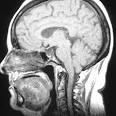

La hipertensión intracraneal (HIC) o hipertensión endocraneana es un trastorno serio en el que la presión del líquido cefalorraquídeo dentro del cráneo es demasiado alta. El líquido cefalorraquídeo (LCR) es un componente fundamental del cuerpo. Protege al cerebro dentro del cráneo, transporta nutrientes al tejido del cerebro y se lleva los deshechos.

Signos y exámenes

Los médicos generales algunas veces pueden notar síntomas iniciales de aumento de la presión intracraneal, como dolor de cabeza, convulsiones o problemas neurológicos. Con frecuencia, con una resonancia magnética o una tomografía computarizada se puede determinar la causa y confirmar el diagnóstico. La presión intracraneal se puede medir durante una punción raquídea (punción lumbar) o también puede medirse directamente utilizando un dispositivo que se introduce a través del cráneo o una sonda (catéter) que se inserta dentro del cerebro.